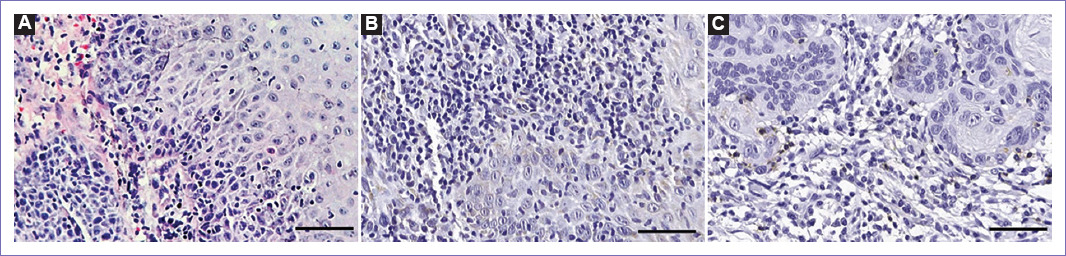

Female patient, 76 years old, white ethnicity, smoker, presented painless lesion in the lower left alveolar ridge. An incisional biopsy was performed and, on histopathological examination, a poorly differentiated squamous cell carcinoma was observed, characterized by: intense pleomorphism, dyskeratosis, nuclear hyperchromatism, atypical mitoses, invasion of underlying tissue, hemorrhagic areas, mild chronic inflammatory infiltrate, and TILs (Fig. 2A). Immunohistochemical analysis revealed the absence of PD-L1 expression and low frequency of CD4+ (Fig. 2B) and CD8+ cells (Fig. 2C), located mainly in the tumor stroma region and around the tumor, respectively.

Figure 2 Case 2. A: Low density of TILs in Hematoxylin and Eosin stain. B: Low frequency of CD4+ cells and C: Low frequency of CD8+ cells. Scale: 50 μm.